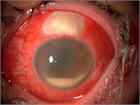

1. 感染性眼内炎とは病原微生物の眼内感染により生じる虹彩毛様体炎、網脈絡膜炎の総称である。

1. 感染性眼内炎の治療は、網膜のダメージを最小限に抑えることが目的である。

1. 急性術後細菌性眼内炎に対しては、早期に硝子体手術および強力な抗炎症療法(ステロイド薬の全身・局所投与)を行う。